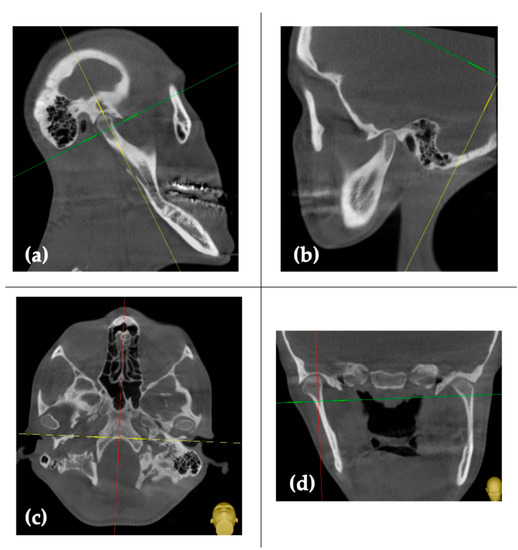

Amazon.com: ビジュアル歯科臨床解剖: 9784781207391: 朱虹: Books。The Use of 3D Technology in the Management of Residual。Concomitant Temporomandibular Joint Replacement and。すべての歯科医師のための臨床解剖学に基づいたComprehensive Dental Surgery折れや破れは無いかと思います。8000円→7500円にお値下げしました。8月14日さらにお値下げしました。。Validation of a patient-specific system for mandible-first。Molecular Biology of the Gene 遺伝子の分子生物学。犬と猫の皮膚病Q&A